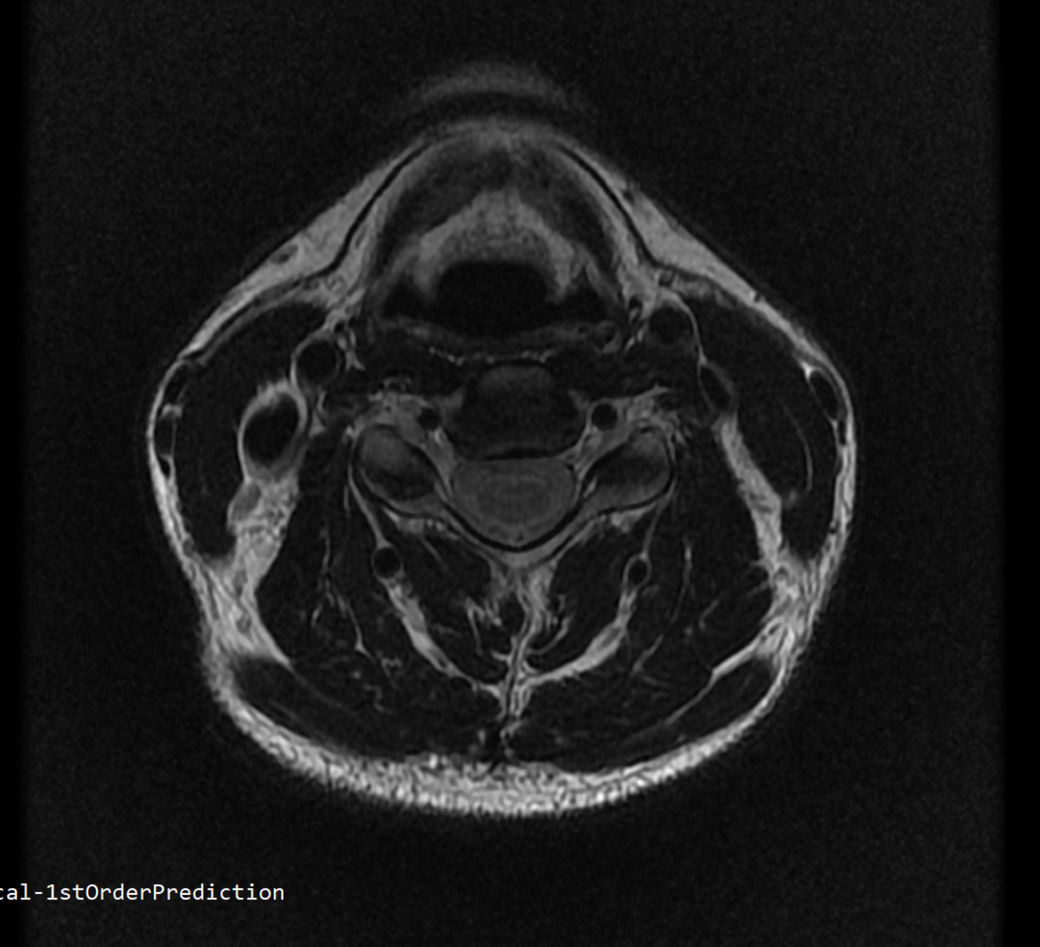

안녕하세요 목 경추 상단부터 순서대로 mri 촬영인데요

전체적으로 봐주시면 감사하겠습니다

• 1번 째 사진